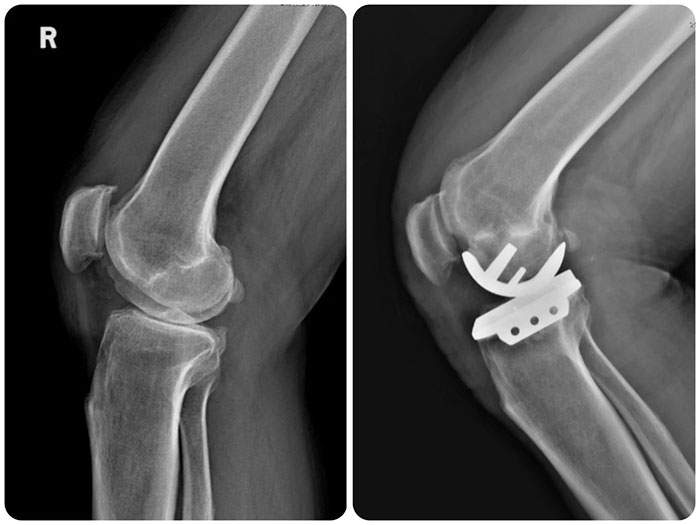

手術中,白玉明主任親自主刀,行膝關節(jié)內側縱向約10cm切口,充分顯露膝關節(jié),探查可見內側間室股骨髁及脛骨平臺軟骨明顯磨損,大部分軟骨下骨裸露,呈骨對骨狀態(tài),髕股關節(jié)及外側間室軟骨Ⅰ~Ⅱ度磨損,前交叉韌帶完整;應用磨具對內側股骨髁及脛骨平臺進行成型,試行屈伸間隙平衡,并進行單髁膝關節(jié)假體安裝。術后第2天患者即可自主下地活動,臨床疼痛癥狀完全消失,膝關節(jié)屈伸活動無受限,患者及家屬對治療效果非常滿意。